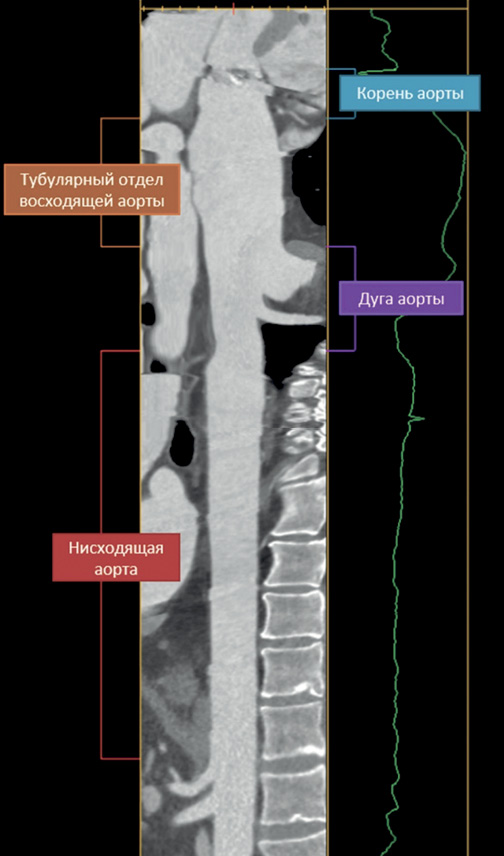

- У пациентов группы с единым устьем для брахиоцефального ствола и левой общей сонной артерией относительно пациентов с нормальной анатомией сосуда группы наблюдается: укорочение тубулярной части восходящей аорты, удлинение корня и дуги аорты, преобладает I тип дуги и реже наблюдается III тип дуги аорты.

Цель. Анализ геометрических параметров грудной аорты у пациентов с аневризмой восходящего отдела в сочетании с нормальной или вариантной анатомией брахиоцефального ствола (БЦС).

Материал и методы. В исследование включено 72 пациента с несиндромными аневризмами восходящей аорты, которые разделены на 2 группы в зависимости от анатомии БЦС: пациенты с единым устьем для БЦС и левой общей сонной артерией (CILCA, n=28) и пациенты с нормальной анатомией сосуда (No CILCA, n=44). На основании данных мультиспиральной компьютерной томографии у всех пациентов проанализированы геометрические особенности восходящего отдела и дуги аорты.

Результаты. По результатам анализа в группах No CILCA и CILCA дополнительно к аневризме тубулярного отдела восходящей аорты отмечена дилатация корня аорты без статистически значимых межгрупповых различий. Длина восходящей аорты в группе No CILCA составила 113 [89; 144] мм vs 108 [63; 143] мм в группе CILCA (p=0,021). При этом длина тубулярного отдела восходящей аорты в группах No CILCA и CILCA составила 86 [63; 123] мм и 82 [40; 103] мм, соответственно (p=0,018). Относительно пациентов группы CILCA у пациентов с нормальной анатомией БЦС чаще диагностировали III тип дуги аорты (27,3% vs 3,6%, p=0,017) и реже I тип дуги аорты (63,6% vs 89,3%, p=0,036).

Заключение. Вариантная анатомия БЦС ("бычья дуга") у пациентов с аневризмой восходящей аорты не обладает негативным профилем в отношении геометрических характеристик грудной аорты по сравнению с пациентами с нормальной анатомией БЦС.